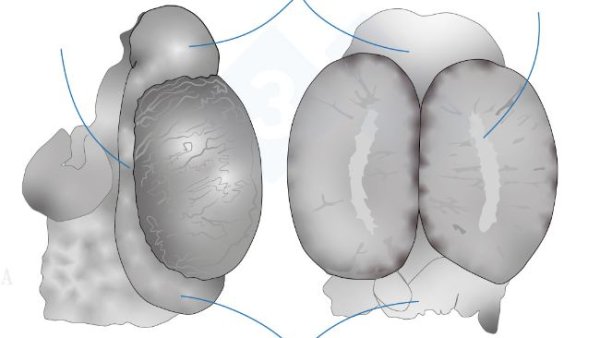

In this second installment, we cover extracting the tongue, trachea, lungs, and heart in one piece. We will extract the organs of the abdominal cavity, both the digestive system and the urinary and genital tracts. In the head, we will access the nasal turbinates, brain, and cerebellum.